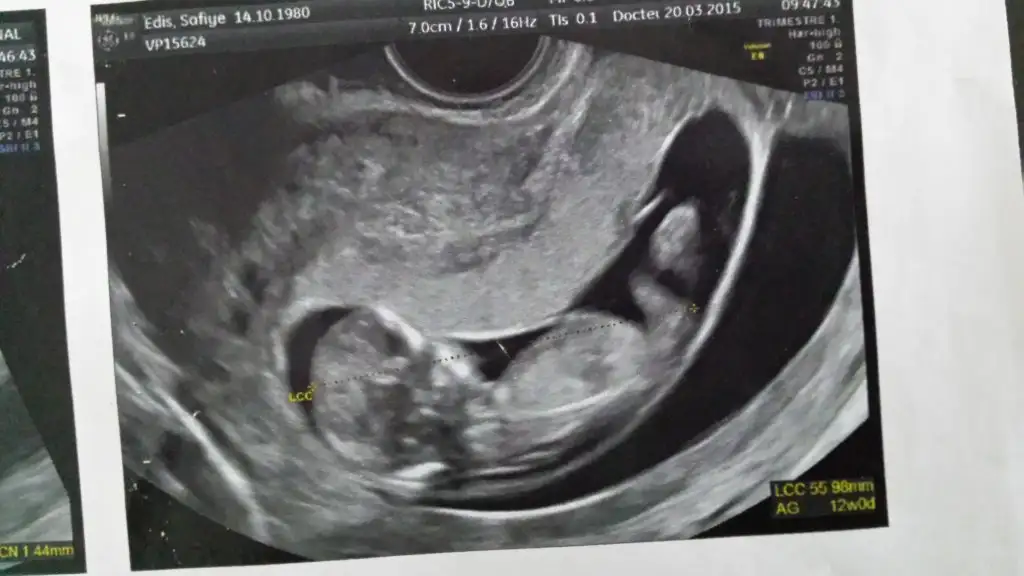

Erkeğe daha çok benzettim ikinci resimden dolayı. Ama kesin diyemem.Kızlar cinsiyet konusunda tahmin alabilirmiyim??Eki Görüntüle 1522208 Eki Görüntüle 1522219

Henüz nubu oluşmamış bu teori için 12-13 haftalar en ideal zamanlar.

Daha vakit var o zaman dimi canımNubu görünmüyor.